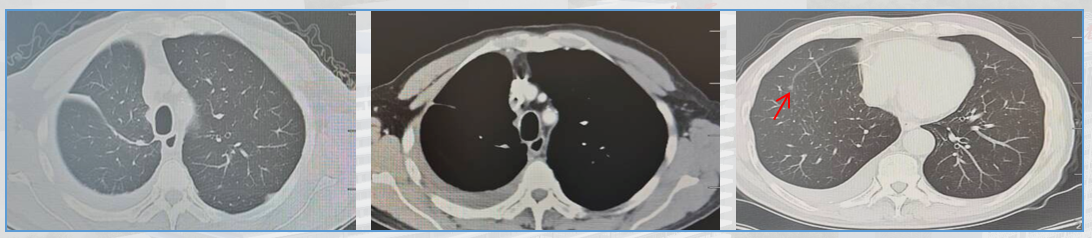

2、2025.4.22行右肺上叶手术,纵隔淋巴结清扫。

术后诊断:右肺上叶恶性肿瘤术后(腺癌);ypT1aN0M0 Ia1期 ;ECOG 1分。

在治疗层面,基于MDT讨论,本病例采用了“新辅助免疫联合化疗→手术→术后辅助免疫”的全程管理模式。治疗结局显著验证了该策略的有效性:术后病理评估显示肿瘤病理学缓解率达99%,接近pCR,并成功实现从cT2bN0M0至ypT1aN0M0的病理学降期。该结果提示患者有望获得长期无病生存。本案例有力证实了该联合治疗模式在局部晚期非小细胞肺癌(NSCLC)患者中具有重要临床应用潜力,也为未来临床实践与研究方向的拓展提供了有益借鉴: